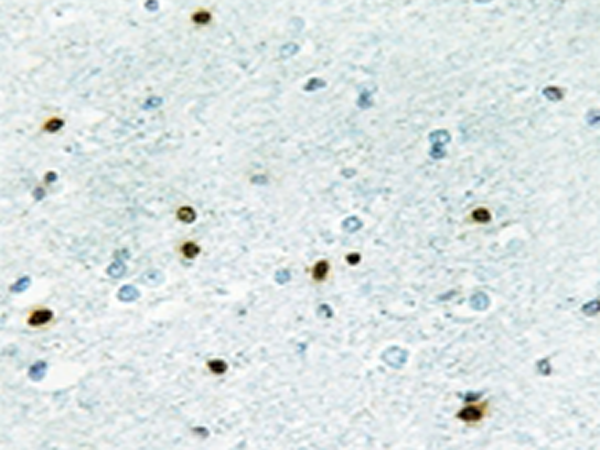

IHC |

IHC positive control: |

Human brain tissue |

IHC Recommend dilution: |

50-100 |